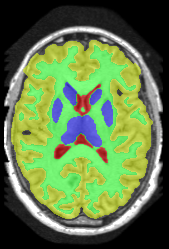

| ground truth | a-exp[7, 8] | QPBO [25, 8] | ours |

We extend [8], which introduced HINTS for arbitrary trees. In [8] a-expansion (a-exp) [7] was used to optimize the multi-label formulation of HINTS, but it often results in bad local minima due to complexities of interaction constraints, e.g. Fig.2. The contribution of [8] is a binary multi-layered HINTS formulation. They use high-order data terms, which are not easy to convert into unary and pairwise potentials for arbitrary trees. Their algorithm’s global optimality guarantee depends on the tree at hand. Only trees that do not yield frustrated cycles [25] have this guarantee, but this is not immediately obvious for any given tree. In [8], non-submodular binary energy implied by frustrated cycles were addressed by QPBO [25]. In practice, QPBO produces only partial solutions for most trees, see Figs. 2, 15 and 17.

3 Optimization

In Section 3.1 we introduce our Path-Move algorithm and in Section 3.2 we show which interaction constraints Path-Move could optimize. The authors in [8] showed that HINTS is non-submodular for a general tree and they used either QPBO or a-exp for optimization. Unfortunately, QPBO does not guarantee to label all pixels and we observed that in our experiments, see Fig. 2. The a-exp algorithm [7] is guaranteed to label all pixels but prone to weak local minima, Fig. 2.

| ground truth | a-exp [7, 8] | QPBO [25, 8] | ours | |

In this application our method outperformed QPBO in most cases and a-exp in all cases. In fact a-exp always converged to a weak local minima in this setting, see Fig. 15. Based on our experience the quality of a-exp result depends on various factors, e.g. tree complexity, the number of min-margins introduced, the order in which labels are expanded, and the initial solution. For the subjects that QPBO was able to find the global optimal Path-Moves either found the global optimal or a very close solution.